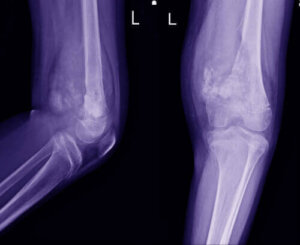

Diagnosen stilles normalt på grundlag af et klinisk interview og sundhedshistorie sammen med nogle tests. Det starter normalt med røntgenstråler, som suppleres med en MR-scanning. En læge vil udføre en biopsi, så snart de opdager et problem og identificerer området.